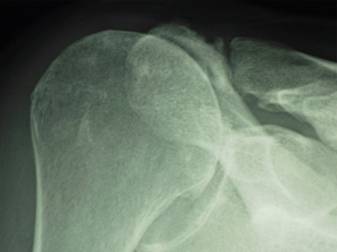

Diagnosis Rotator cuff tear arthropathy (or shoulder arthritis with a large rotator cuff tear) is diagnosed by a history of progressive loss of shoulder function usually without an injury along with a physical examination showing weakness and grinding on movement and a typical appearance on X-ray. In these films the humeral head can be seen contacting the undersurface of the coracoacromial arch (see arrows). [Figure 6] Diagnostic tests The most important test for cuff tear arthropathy is the x-ray characteristically showing rounding off of the humeral head as it contacts with the undersurface of the coracoacromial arch. [Figure 7] Effects There is usually no significant discomfort during the diagnosis of rotator cuff tear arthropathy. Health care team Rotator cuff tear arthropathy (arthritis of the shoulder associated with a massive cuff tear) is best diagnosed by an orthopedic surgeon with experience in shoulder disorders. Finding a doctor When severe special surgical procedures such as a prosthetic replacement with at CTA head or a reverse Delta (reversed) prosthesis may be indicated in contrast to management with a total shoulder joint replacement. Certain doctors specialize in rotator cuff tear arthropathy (arthritis of the shoulder associated with a massive cuff tear). Such individuals may be found in the shoulder services of major schools of medicine. |